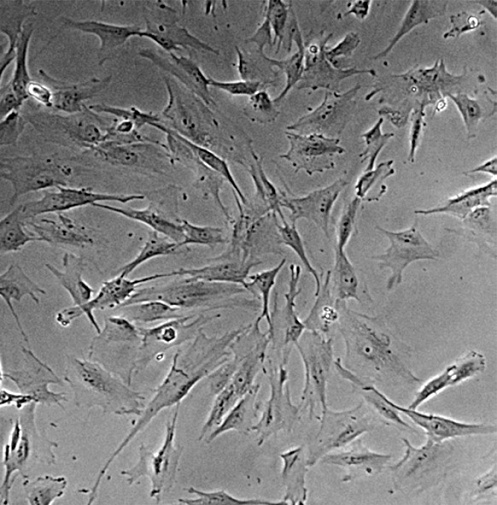

Морфология:

фибробластоподобная

Способ культивирования:

монослойный